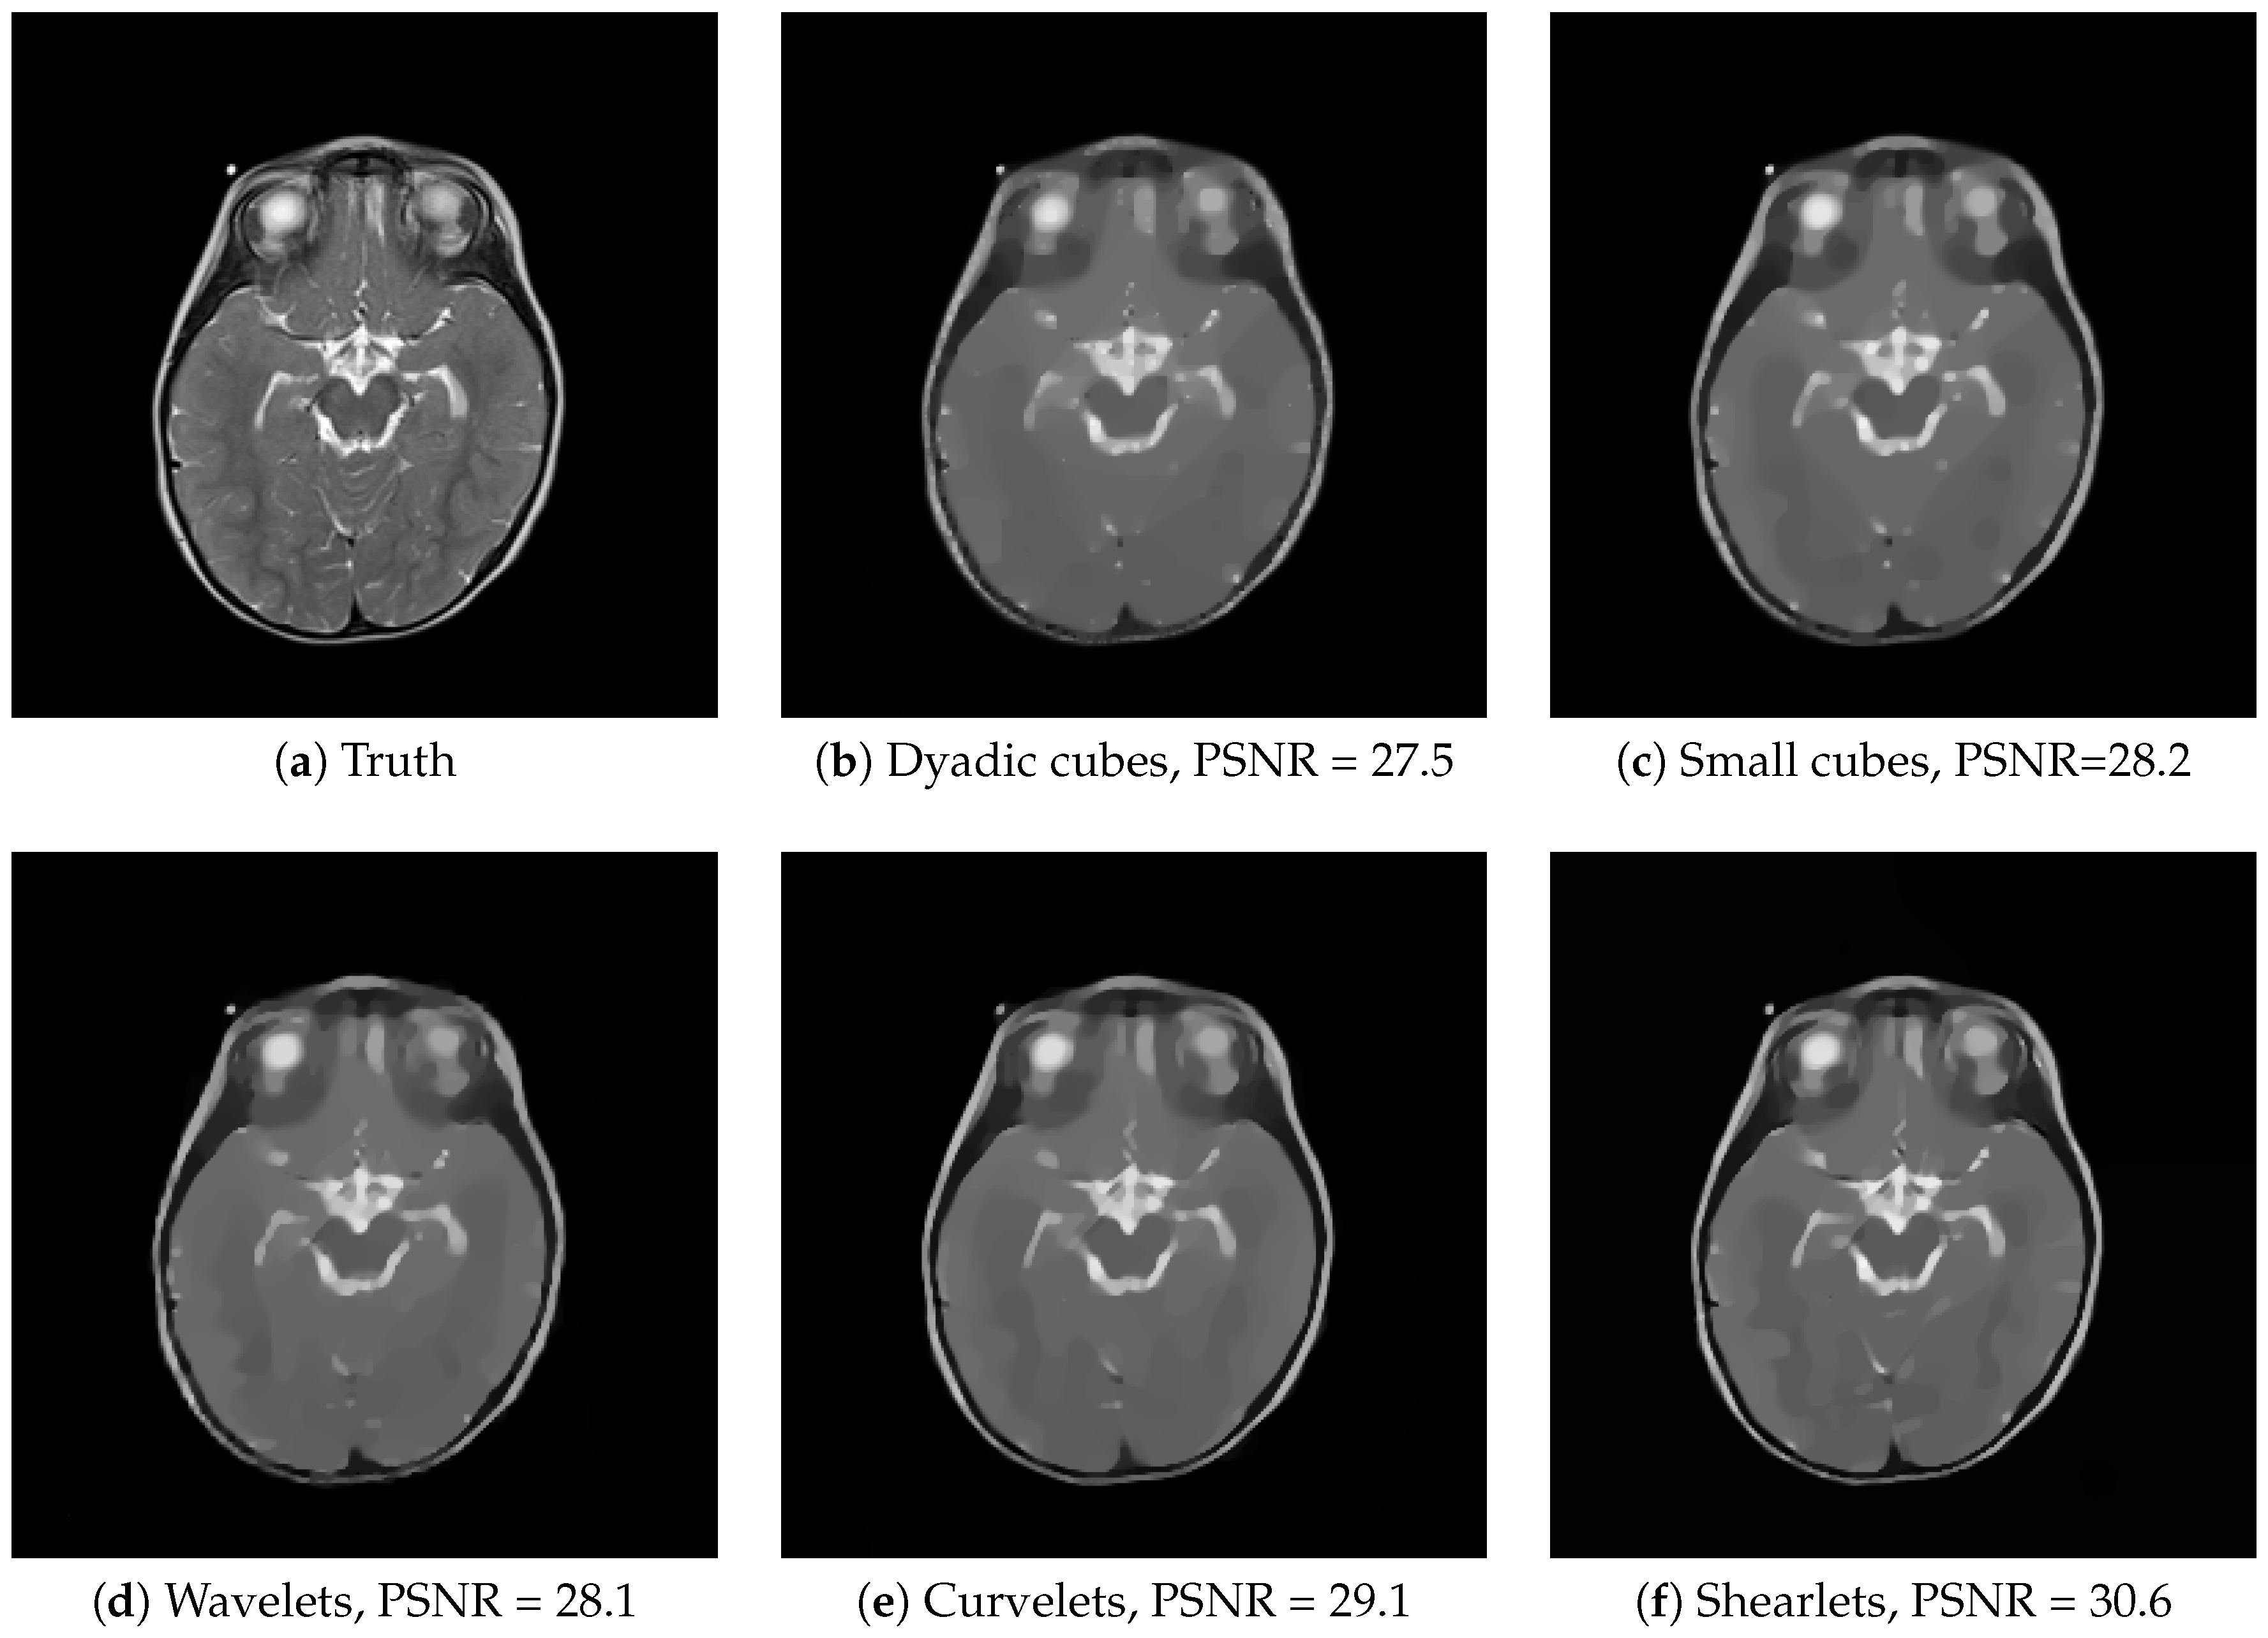

4.2. Comparison of Different Dictionaries

| Dyadic Cubes | Small Cubes | Wavelets | Curvelets | Shearlets | ||

|---|---|---|---|---|---|---|

| “brain” | MISE | 0.00176 (5.4 ) | 0.00149 (1.9 ) | 0.00147 (2.9 ) | 0.0013 (2.5 ) | 0.000871 (3 ) |

| PSNR | 27.5 (0.013) | 28.3 (0.0055) | 28.3 (0.085) | 28.9 (0.086) | 30.6 (0.015) | |

| SSIM | 0.871 (3.1 ) | 0.806 (0.002) | 0.872 (0.0023) | 0.852 (0.0091) | 0.715 (0.0043) | |

| VIF | 0.726 (0.00058) | 0.823 (0.00036) | 0.767 (0.0021) | 0.809 (0.0022) | 0.852 (0.00086) | |